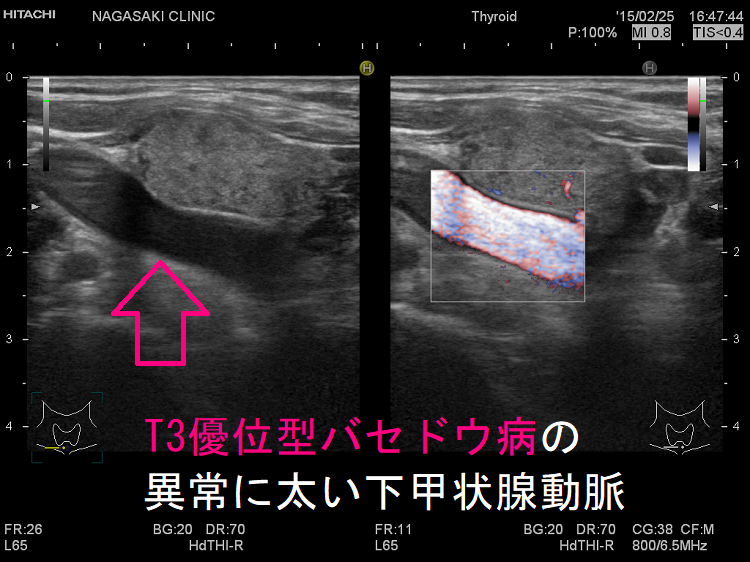

ケース④ 一度も甲状腺機能正常化したことが無く、甲状腺全摘手術に

難治性T3優位型バセドウ病 下甲状腺動脈血流速度(ITA-PSV)も高値で85.3cm/sでした。

難治性T3優位型バセドウ病は若年女性に多く、甲状腺組織の2型脱ヨード酵素(DIO 2)活性が異常に高いため、FT4に比べFT3が著明高値になる。巨大甲状腺腫、TSH レセプター抗体(TRAb)異常高値、甲状腺超音波エコー検査で下甲状腺動脈は異常に太く、下甲状腺動脈血流速度ITA-PSVも異常高値。薬物治療抵抗性で、FT4正常化してもFT3は高値、再発繰り返す。I-131治療は1回で終わらず、甲状腺全摘出手術になる。服薬アドヒアランス不良は患者がメルカゾール・プロパジールを服用しない事。難治性バセドウ病と思って薬を増やしても、甲状腺ホルモンは下がらない。

- 甲状腺超音波(エコー)検査で、下甲状腺動脈が異常に太く、下甲状腺動脈血流速度(ITA-PSV)が異常高値